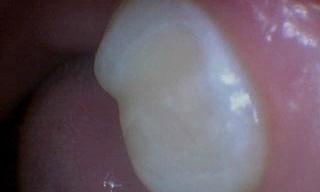

A patient from Chester, NH was having pain on his lower tooth due to a large cavity. The tooth needed a composite restoration, and the patient was grateful his pain went away.